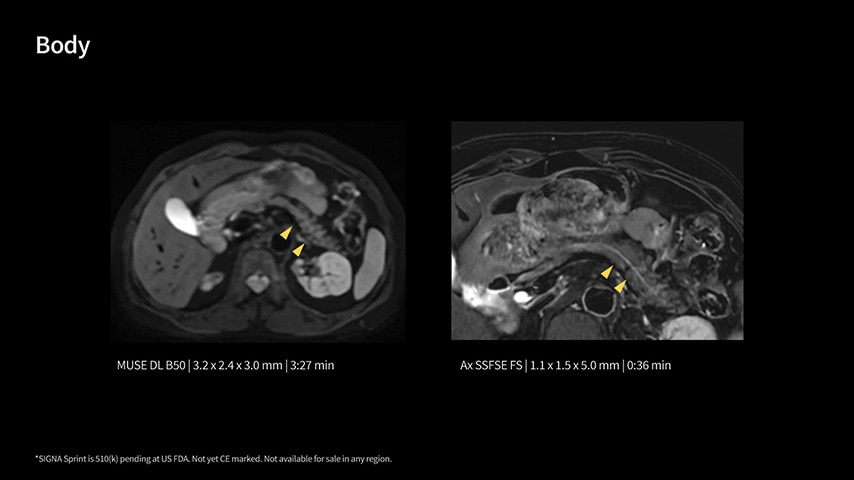

In oncological assessments, diffusion imaging is a critical clinical indicator. SIGNA Sprint offers clearer diffusion, reduced distortion, and improved SNR.¹

Within cardiovascular diseases, the functional assessment of the heart is an essential imaging application. SIGNA Sprint is powered by built-in AI technologies—Sonic DL™, AIR Recon DL and AIR x™—enabling high-quality imaging even in the most demanding anatomies.

The growing clinical need within oncology and cardiology requires an MRI scanner that can rise to the challenge. With a high gradient performance of 65/200, SIGNA Sprint helps deliver crystal-clear imaging for ultimate diagnostic confidence. Improved signal-to-noise ratio (SNR) and diffusion, with deep-learning solutions that could enhance diagnostics and treatment response monitoring in your oncology patients.¹ Additionally, the shift from qualitative to quantitative cardiac MRI reduces the time and expertise needed to interpret scans and offers greater consistency and reliability. Helping you to unlock the power to explore further - even in your most challenging cases.

With GE HealthCare's comprehensive suite of deep-learning solutions integrated into SIGNA Sprint, you can unlock the full potential of your MRI system. No need for complicated patient setups or imaging protocols. The exceptional intelligence of our AI solutions offer multiple benefits, with AIR Recon DL giving pin-sharp images, Sonic DL accelerating scans up to 12x, and AIR x enabling automated slice placement. All helping to enhance your department’s workflow efficiency, increase patient throughput, and get the diagnostic clarity you need, faster.¹ Meaning you can spend more time on what truly matters—personalized patient care, enabling optimized treatment plans and treatment response monitoring—ultimately, supporting better clinical outcomes.